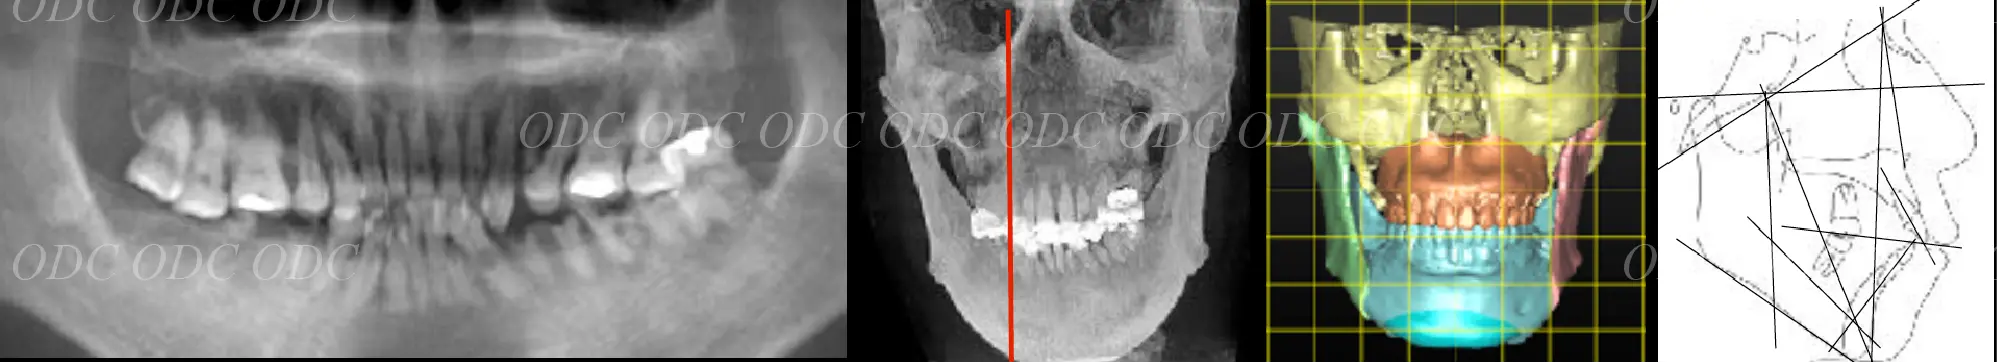

2011年、噛めないという主訴で65歳の男性が来院されました。

全顎的な治療を希望されていましたので、口腔内はもちろん骨格・顔貌・顎関節の診断を行い治療目標を設定致しました。

上顎天然歯に関しては矯正治療、下顎にはフルマウスのインプラント治療を計画致しました。

顎関節の安定を確認した後、矯正治療とインプラント治療を並行して行いました。

約3年の治療期間を経て、計画通りの満足のいく結果を獲得することができました。

2014年、治療終了時の口腔内の状態です。

インプラント上部構造はCADCAMによって作成されたジルコニアの上部構造です。

2024年、治療終了後約10年が経過いたしました。

顎関節を考慮した包括的な治療を行うことで咬合状態(噛み合わせ)は現在もとても安定した状態です。